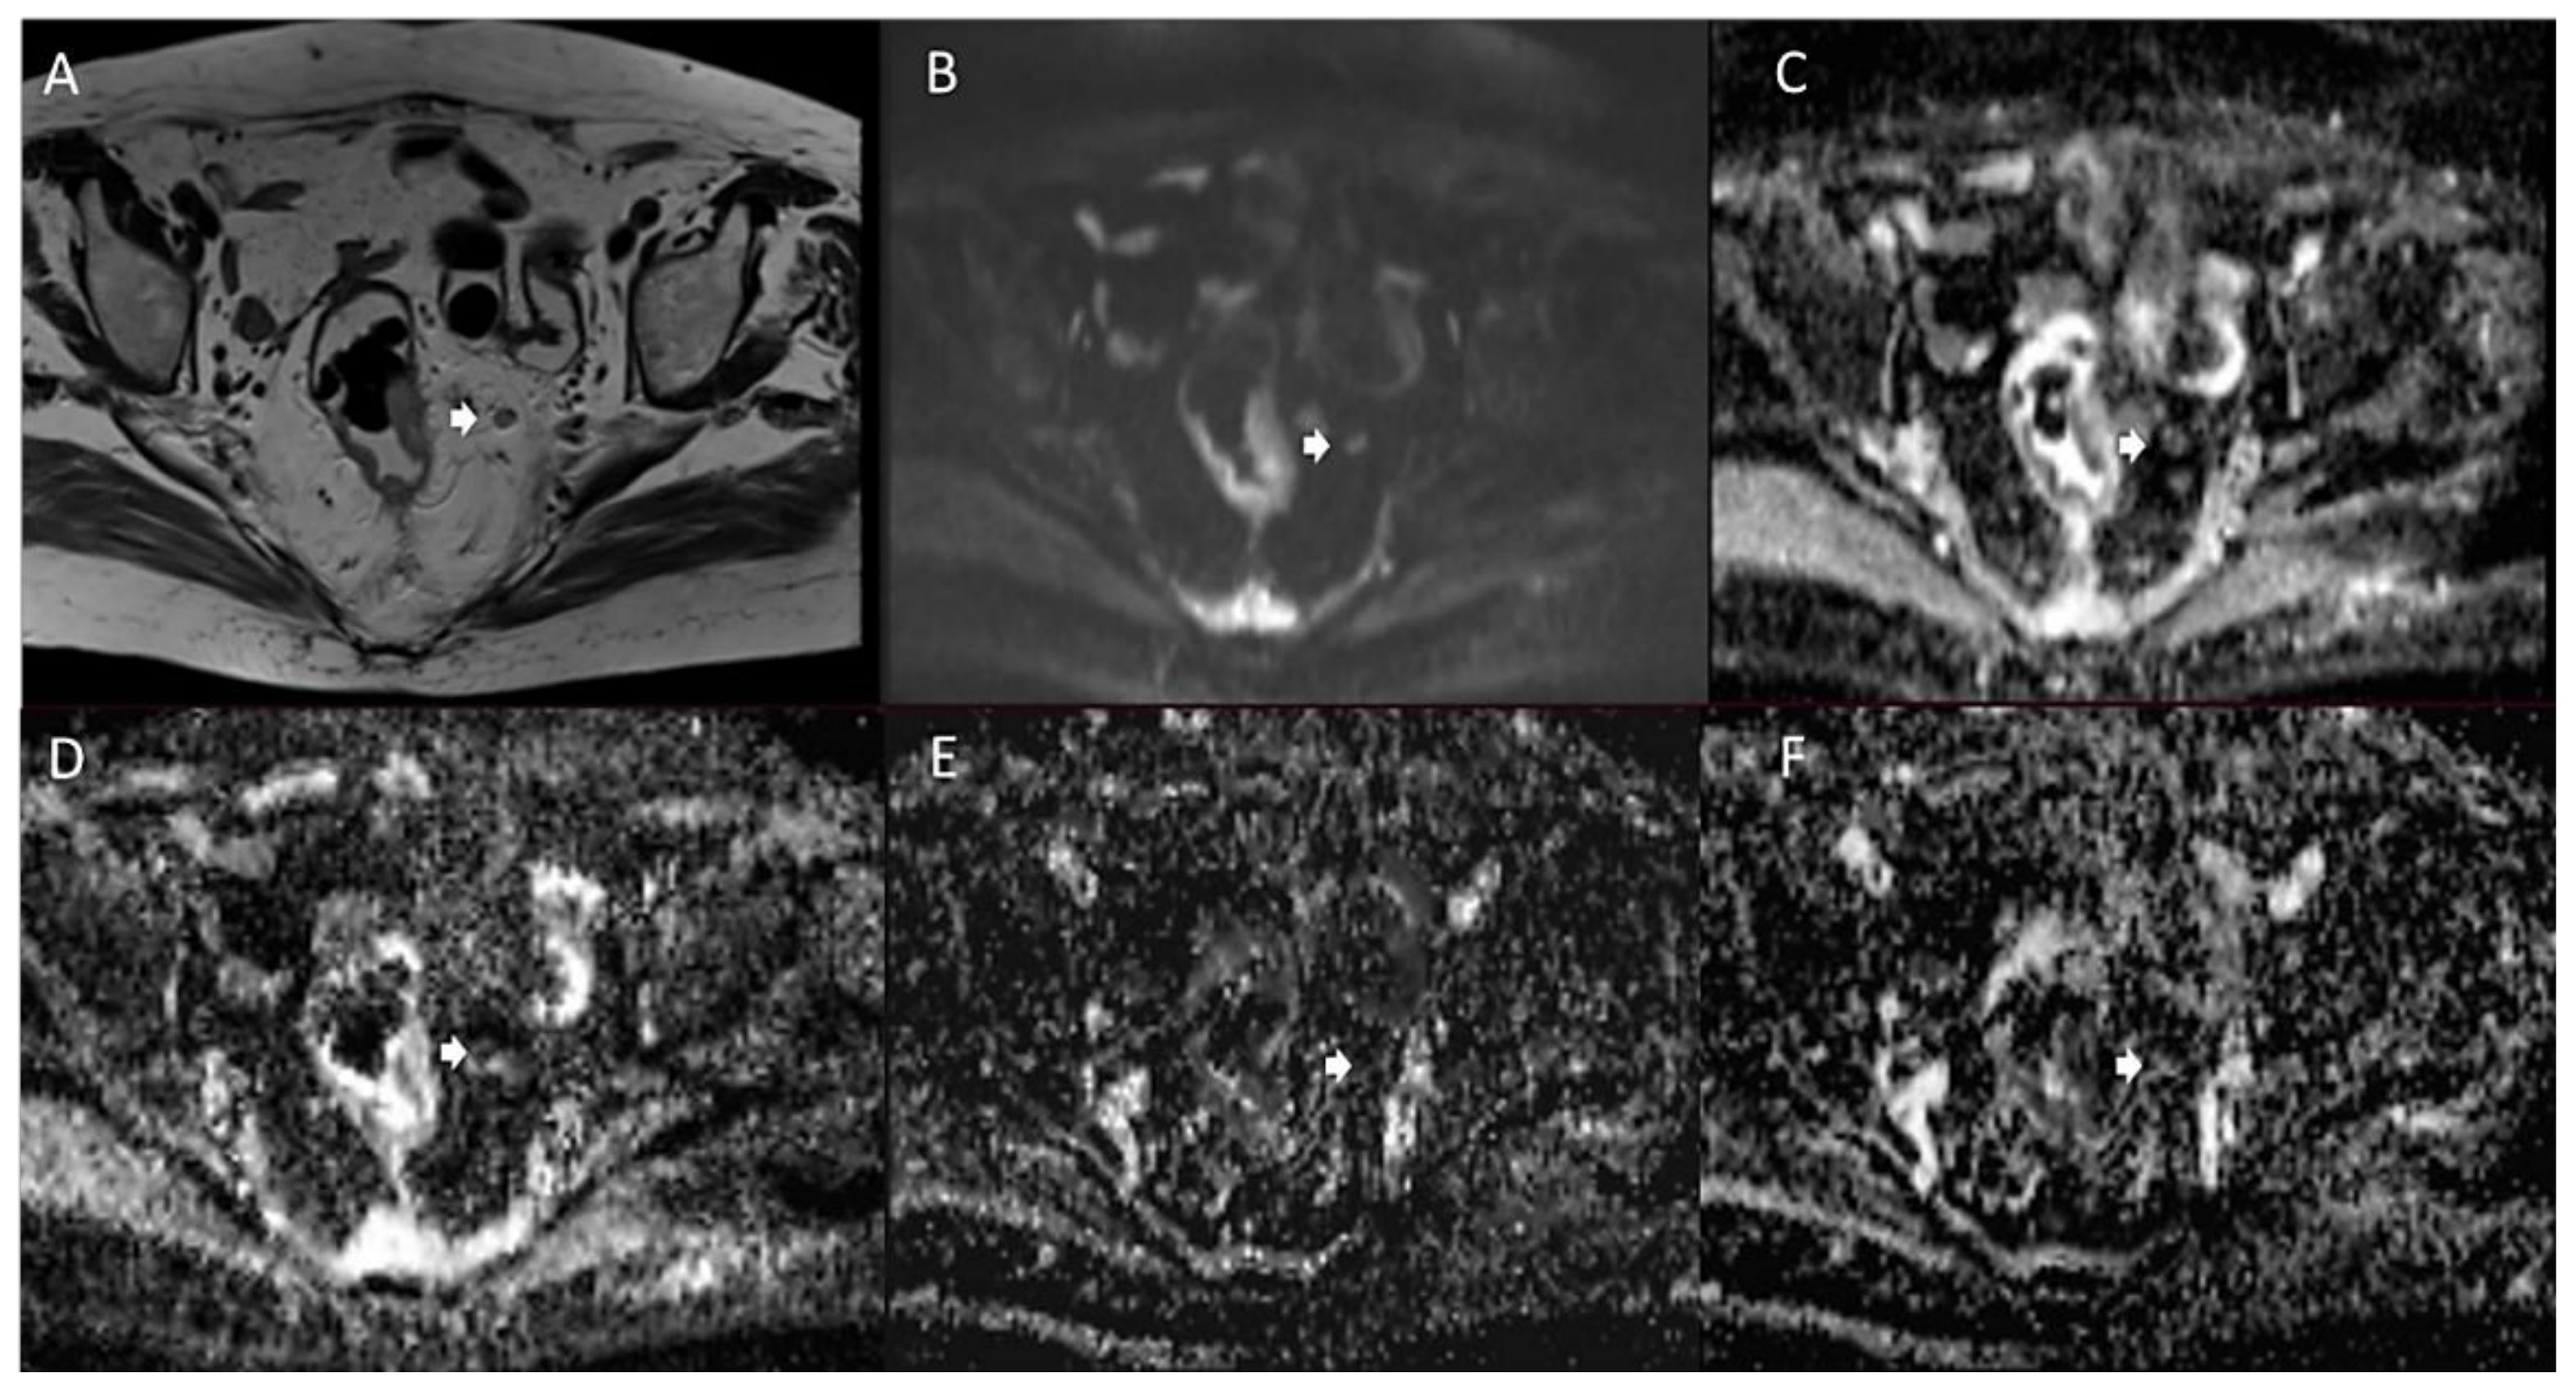

- Armbruster, M.; D’Anastasi, M.; Holzner, V.; Kreis, M.E.; Dietrich, O.; Brandlhuber, B.; Graser, A.; Brandlhuber, M. Improved Detection of a Tumorous Involvement of the Mesorectal Fascia and Locoregional Lymph Nodes in Locally Advanced Rectal Cancer Using DCE-MRI. Int. J. Color. Dis. 2018, 33, 901–909. [Google Scholar] [CrossRef]

- Grøvik, E.; Redalen, K.R.; Storås, T.H.; Negård, A.; Holmedal, S.H.; Ree, A.H.; Meltzer, S.; Bjørnerud, A.; Gjesdal, K.-I. Dynamic Multi-Echo DCE- and DSC-MRI in Rectal Cancer: Low Primary Tumor K(Trans) and ΔR2* Peak Are Significantly Associated with Lymph Node Metastasis. J. Magn. Reson. Imaging 2016, 46, 194–206. [Google Scholar] [CrossRef] [Green Version]

- Yu, X.; Wen, L.; Hou, J.; Wang, H.; Lu, Q. Discrimination of Metastatic from Non-Metastatic Mesorectal Lymph Nodes in Rectal Cancer Using Quantitative Dynamic Contrast-Enhanced Magnetic Resonance Imaging. J. Huazhong Univ. Sci. Technol. Med. Sci. 2016, 36, 594–600. [Google Scholar] [CrossRef]